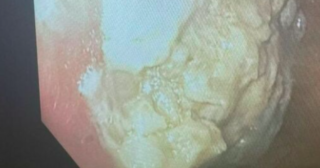

Un bambino di 4 anni dell’Ohio ha mangiato un’intera confezione di chewing-gum ed è finito all’ospedale rischiando la vita. L’immagine dell’esito dell’esofagoscopia del bimbo di 4 anni dell’Ohio sta facendo il giro dei tabloid. Un’enorme massa di gomma da masticare – senza zucchero- appiccicata a oltre il 25% delle pareti dello stomaco.

I medici hanno inserito un esofagoscopio, un tubo di metallo cavo, nella gola e hanno usato una pinza per cercare di staccare pezzi di gomma che sono stati successivamente estratti. Gli è stato detto dai medici che era fortunato che la gomma non gli avesse bloccato l’intestino, il che avrebbe potuto essere fatale, ma non ha subito effetti a lungo termine dalla procedura.